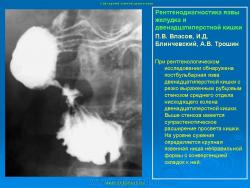

Пищеварительная система. Рентгенодиагностика язвы желудка и 12-ти перстной кишки. +

Рентгенодиагностика язвы желудка и 12-ти перстной кишки.

Данная статья помещена не только с познавательной целью, но и в дискуссионном плане.